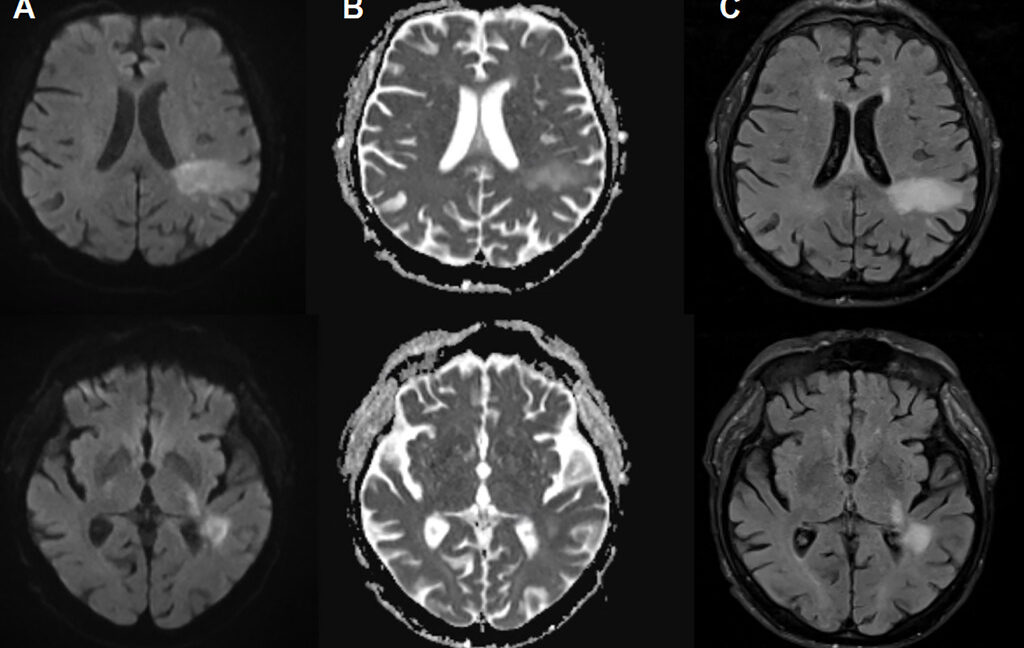

Lorsque le JC virus atteint le cerveau, il provoque une affection appelée leucoencéphalopathie multifocale progressive (LEMP). Cette maladie détruit la gaine de myéline qui protège les cellules nerveuses, entraînant une détérioration neurologique rapide. Les symptômes peuvent inclure une faiblesse musculaire, des troubles de la vision, des difficultés d’élocution, des changements de personnalité et un déclin cognitif. Sans la myéline, les signaux nerveux ne peuvent pas être transmis correctement, ce qui entraîne une perte progressive des fonctions cérébrales.

Le pronostic de la LEMP reste sombre. Avant l’ère des traitements antirétroviraux modernes, la maladie était presque toujours mortelle en quelques mois. Aujourd’hui, avec une restauration immunitaire rapide, certains patients peuvent survivre, mais beaucoup restent avec des handicaps neurologiques permanents. Le taux de mortalité demeure élevé, soulignant l’importance de la surveillance chez les patients immunodéprimés.